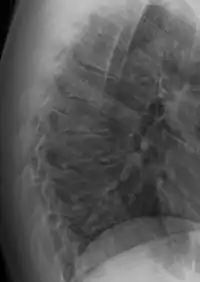

| Scheuermann's disease | |

| Other names | Scheuermann's kyphosis, Calvé disease, idiopathic juvenile kyphosis of the spine |

| Scheuermann's disease on lateral Xray of the T spine | |

Scheuermann's disease is a self-limiting skeletal disorder of childhood. Scheuermann's disease describes a condition where the vertebrae grow unevenly with respect to the sagittal plane; that is, the posterior angle is often greater than the anterior. This uneven growth results in the signature "wedging" shape of the vertebrae, causing kyphosis. It is named after Danish surgeon Holger Scheuermann.[3][4][5]

Diagnosis is typically by medical imaging. The degree of kyphosis can be measured by Cobb's angle and sagittal balance.